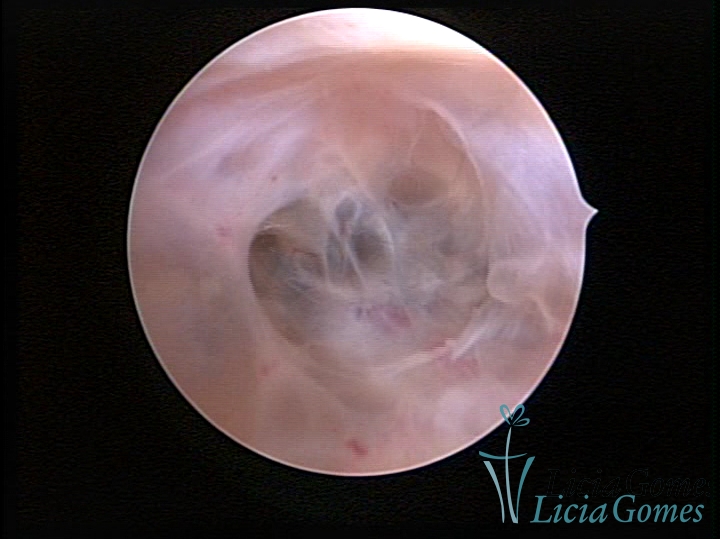

FIBROUS SYNECHIA

Uterine synechiae are scars (adherence) between the surface of the uterine walls, which may occur after the surgical procedure, uterine curettage, or after an inflammatory process in the uterine cavity (endometritis), which may lead to menstrual changes, infertility and obstetric complication such as abortion and premature birth.